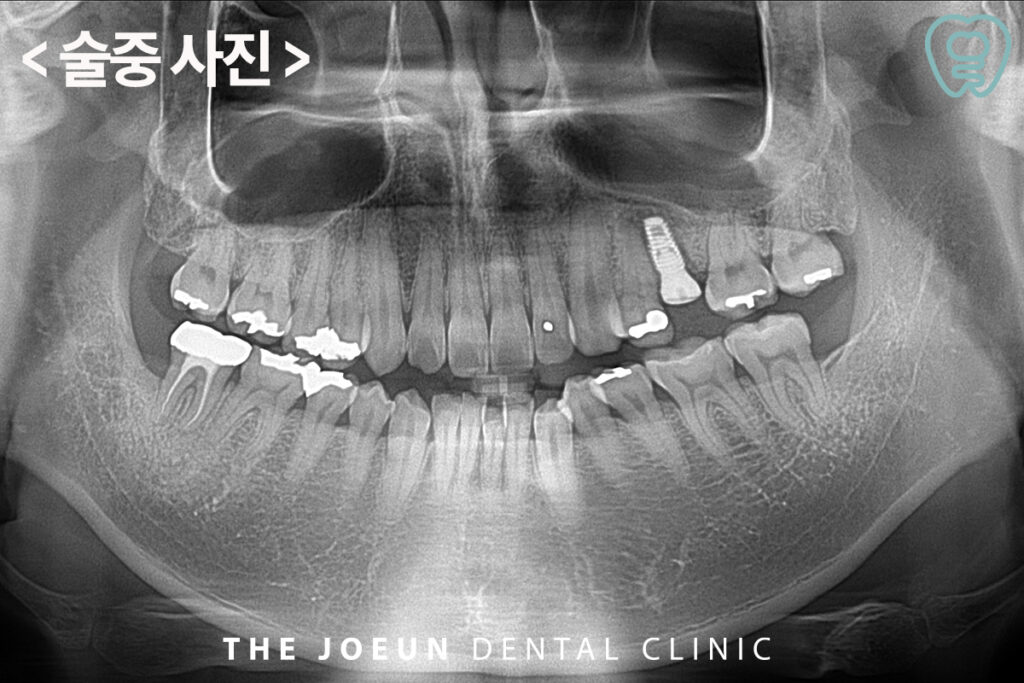

오늘은 발치하신 지 오래되어 위축된 치조골에 임플란트를 3개월이라는 단기간 안에 마무리하신 환.자분을 소개해 드리려고 합니다.

환.자분께서는 왼쪽 위 작은 어금니 부위 임플란트 치료를 받으시고 싶으시다며 내원해 주셨는데요. 치아를 상실하신 지 오래되어, 눈으로 보기에도 잇몸뼈가 많이 위축되어 있었습니다.

보다 정밀하게 잇몸뼈의 양과 질을 판단하기 위해 CT를 촬영해 보았는데요.

파란색 점선을 보는 것과 같이, 입천장 쪽으로 잇몸뼈가 많이 소실되어 있음을 확인할 수 있었습니다. 따라서 부족한 잇몸뼈를 보충하는 뼈이식을 동반한 임플란트 식립을 계획하였습니다.

뼈이식을 동반하여 임플란트를 식립한 모습인데요. 파란색 점선으로 표시된 기존 입천장 쪽으로 소실되었던 뼈의 두께와 빨간색으로 표시된 부분이 이식한 뼈의 양을 표시한 것입니다.